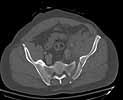

Was hemodynamic unstable at local ER, sent to our Trauma center where circumferential pelvic binder placed and pt. stabilized with fluid, blood, and rewarming. Angiography not performed. An extraperitoneal bladder disruption was found, uro elected to treat non-operatively. Initial xray (not shown) demonstrated 5-7 cm wide at symphysis and SI joint. The first image attached is of CT once binder is in place.